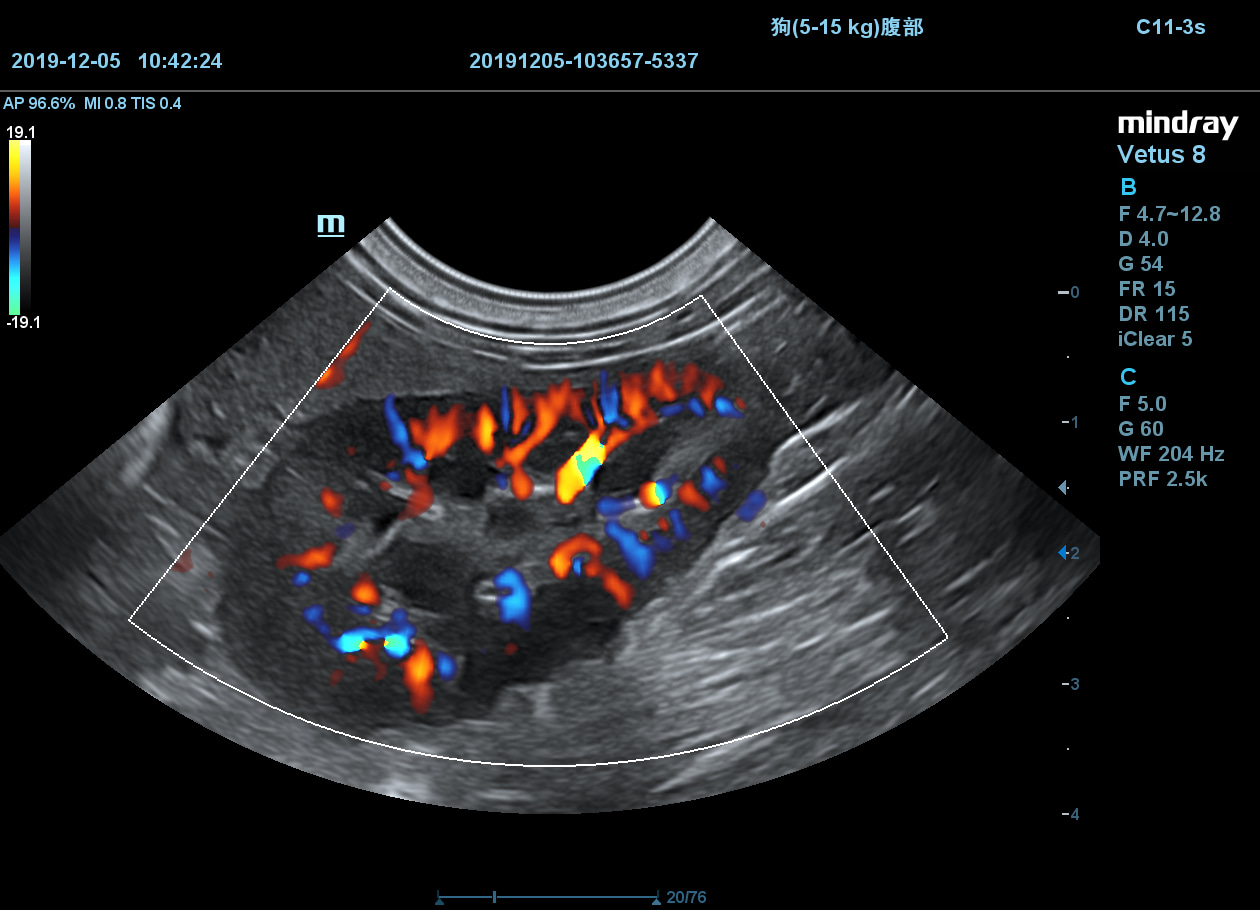

Mindray vetus